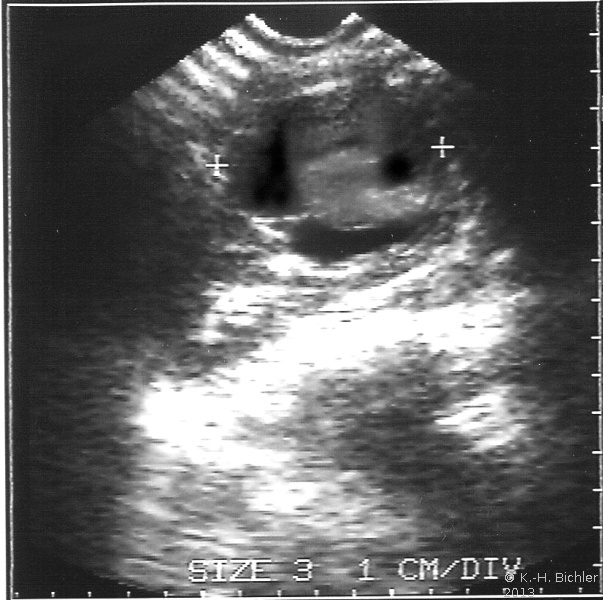

Am Beginn der Diagnostik steht die Sonographie (Abbildung 6). Neben dem Tumornachweis und der Zugehörigkeit zur Niere ist der Nachweis einer eventuellen Tumorinvasion in die Nierenvene (u.U. im Rahmen einer farbkodierten Dopplersonographie) bzw. in die Vena Cava inferior von Interesse. Immerhin bricht der Tumor in 11% in die Nierenvene und zu 6% in die Vena Cava ein, selten bis in das rechte Atrium (s. auch Abbildung 1c)

Der Wert der FKDS (farbkodierte Dopplersonographie= Angiodynographie = Farbdoppler) bzw. der kontrastverstärkten Sonographie ist zur Zeit noch nicht hinreichend belegt. Eine Verbesserung der Ergebnisse, auch hinsichtlich der Beurteilung der Nierenvene (z.B. Tumoreinbruch) ist zu erwarten